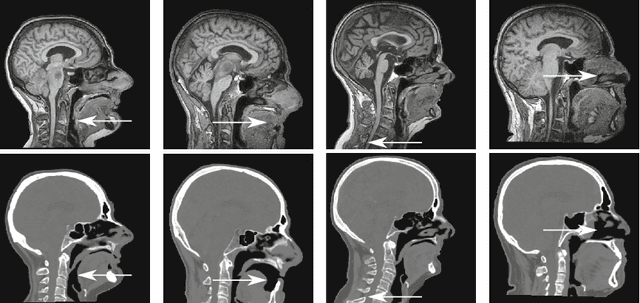

MR-only radiotherapy treatment planning requires accurate MR-to-CT synthesis. Current deep learning methods for MR-to-CT synthesis depend on pairwise aligned MR and CT training images of the same patient. However, misalignment between paired images could lead to errors in synthesized CT images. To overcome this, we propose to train a generative adversarial network (GAN) with unpaired MR and CT images. A GAN consisting of two synthesis convolutional neural networks (CNNs) and two discriminator CNNs was trained with cycle consistency to transform 2D brain MR image slices into 2D brain CT image slices and vice versa. Brain MR and CT images of 24 patients were analyzed. A quantitative evaluation showed that the model was able to synthesize CT images that closely approximate reference CT images, and was able to outperform a GAN model trained with paired MR and CT images.